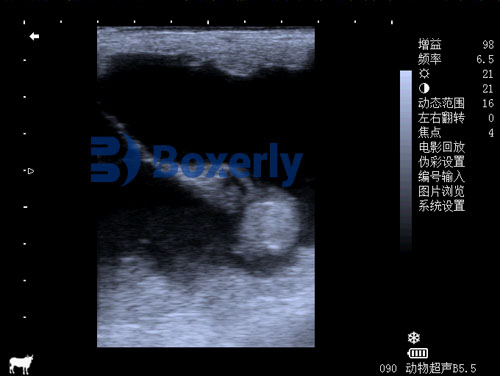

What a Normal Fetal Heartbeat Looks Like

A healthy fetal heartbeat in a mare usually starts showing up clearly on ultrasound by day 25 to 30 of pregnancy. In early stages, it may flicker rapidly—often around 120 to 180 beats per minute. That’s normal. As the pregnancy progresses, the rate slows slightly but remains much faster than the mare’s own resting heart rate.

What we’re watching for isn’t just the number of beats per minute, though. We’re looking for consistency, rhythm, and strength. Is the beat steady? Is it responding appropriately when the fetus moves? These small details offer big insights.